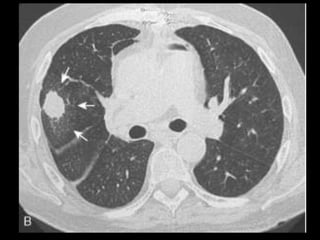

Malformação arteriovenosa(MAV) TC:o aspecto típico é de uma massa regular, lobulada, redonda ou oval, ou até o de uma formação serpenginosa, com menos de 1 cm a vários cm de tamanho, associada a uma artéria nutriz visivelmente aumentada e uma veia de drenagem alargada; Uma ANGIO-TC geralmente faz o diagnóstico; Tratamento pode ser realizado com terapia embólica.

TC: o aspecto típico é de uma massa regular,

lobulada, redonda ou oval, ou até o de uma

formação serpenginosa, com menos de 1 cm a

vários cm de tamanho, associada a uma artéria

nutriz visivelmente aumentada e uma veia de

drenagem alargada;

Uma ANGIO-TC geralmente faz o diagnóstico;

Tratamento pode ser realizado com terapia

embólica.

MAV complexa